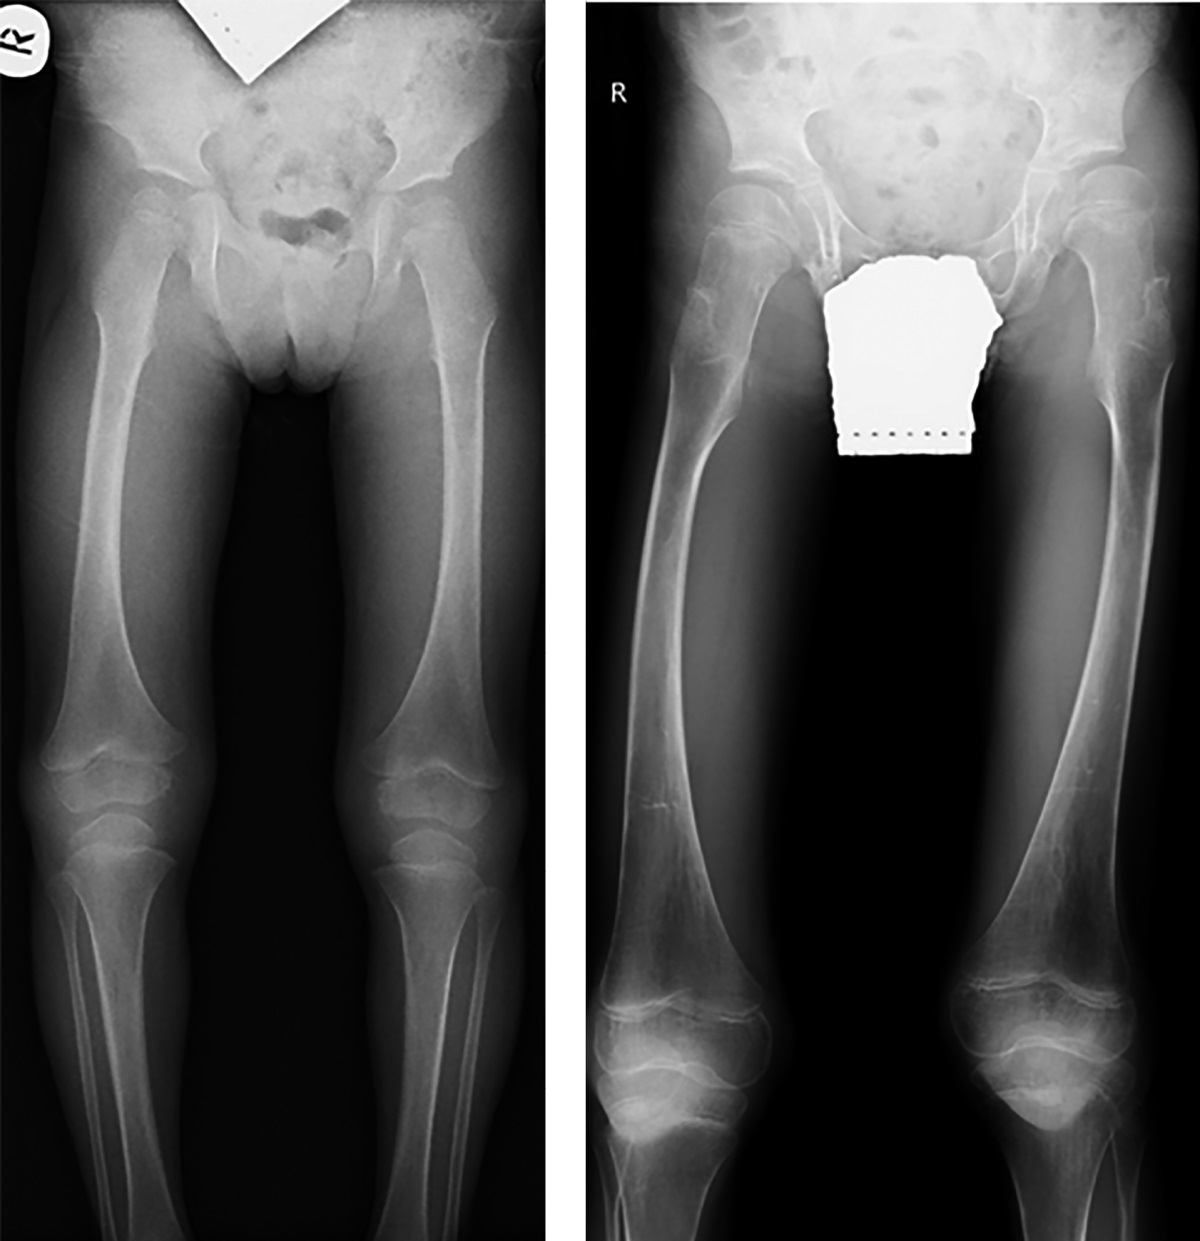

Рисунок 1. Пациентка №1, 2 года 8 мес., с синдромом Хатчинсона-Гилфорда.

Рентгенография таза с захватом нижних конечностей на протяжении. Форма и структура эпифизов и метафизов бедренных костей изменена.

При первичном обследовании в возрасте 2-х лет 8 месяцев у девочки наблюдалась прогрессирующая задержка роста и дефицит массы тела, классический прогероидный фенотип (мраморные, сухие кожные покровы, выраженная венозная сеть на голове, выраженный периорбитальный цианоз, цианоз носогубного треугольника, генерализованная липодистрофия, клювовидный нос, микрогнатия, шарообразные глаза, экзофтальм, тотальная алопеция, отсутствие бровей), генерализованная липодистрофия, гепатопатия, дислипидемия. При осмотре ортопедом выявлены множественные контрактуры мелких суставов кистей, а также более крупных — тазобедренных, коленных, голеностопных суставов (табл. 2). По данным рентгенографии, отмечены изменения формы и структуры эпифизов и метафизов бедренных костей (рис. 1).